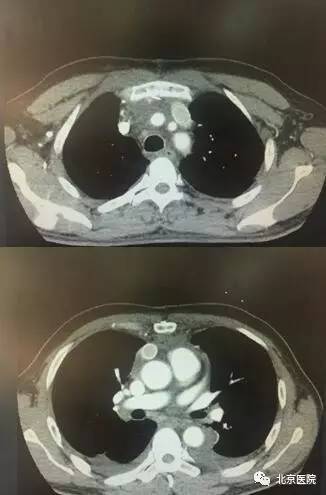

患者术前、术后对比

该患者系43岁男性,2周前出现颜面部肿胀,晨起明显,近1周来颜面部肿胀逐渐加重,颈部浅静脉怒张,前胸壁皮下静脉迂曲扩张。胸部CT提示前纵隔恶性肿瘤,外侵明显,与周围组织界限难以分清;左无名静脉及上腔静脉内瘤栓形成,上腔静脉几乎完全堵塞。面对如此复杂的病情当地医院难以完成如此复杂的手术,患者为进一步治疗于2017年3月8日来到北京医院胸外科。

CT术前、术后对比

面对如此复杂、困难的手术,胸外科佟宏峰主任率领的医护团队勇于挑战、知难而上,经过详细的术前讨论和准备,制定了周密的手术计划和围术期管理方案。在手术麻醉科医护人员的大力配合与协助下,北京医院胸外科团队于2017年3月15日在全麻下为该患者实施了前纵隔肿瘤切除、双肺上叶部分切除、心包部分切除、上腔静脉切除、左侧无名静脉切除、部分右侧无名静脉切除、左侧无名静脉-右心房搭桥、右侧无名静脉-上腔静脉搭桥术。该手术共历时5个小时,完整切除前纵隔恶性肿瘤,并顺利完成血管重建。术后经过严密的监测、精心的治疗及护理,该患者恢复顺利,上腔静脉梗阻的症状明显缓解,复查胸部CT显示重建的血管内血流通畅,效果良好,术后第7天顺利出院。